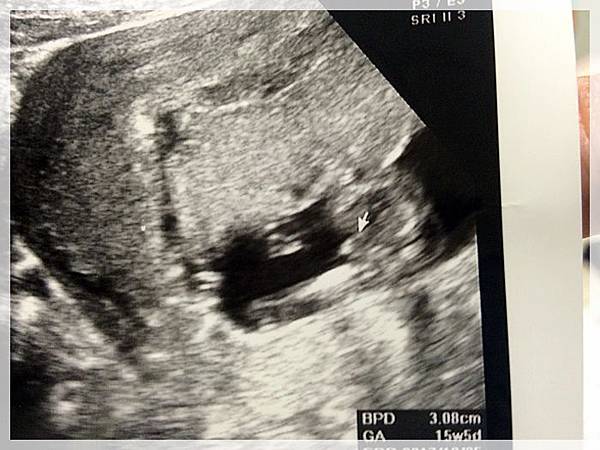

2017.05.08 紜紜6y06m02d 妞妞4y03m29d

今天我們去產檢,來去看樂樂囉![]()

樂樂有乖乖的長大...

醫生叔叔也說確定樂樂是男生不是在下面比讚喔![]()